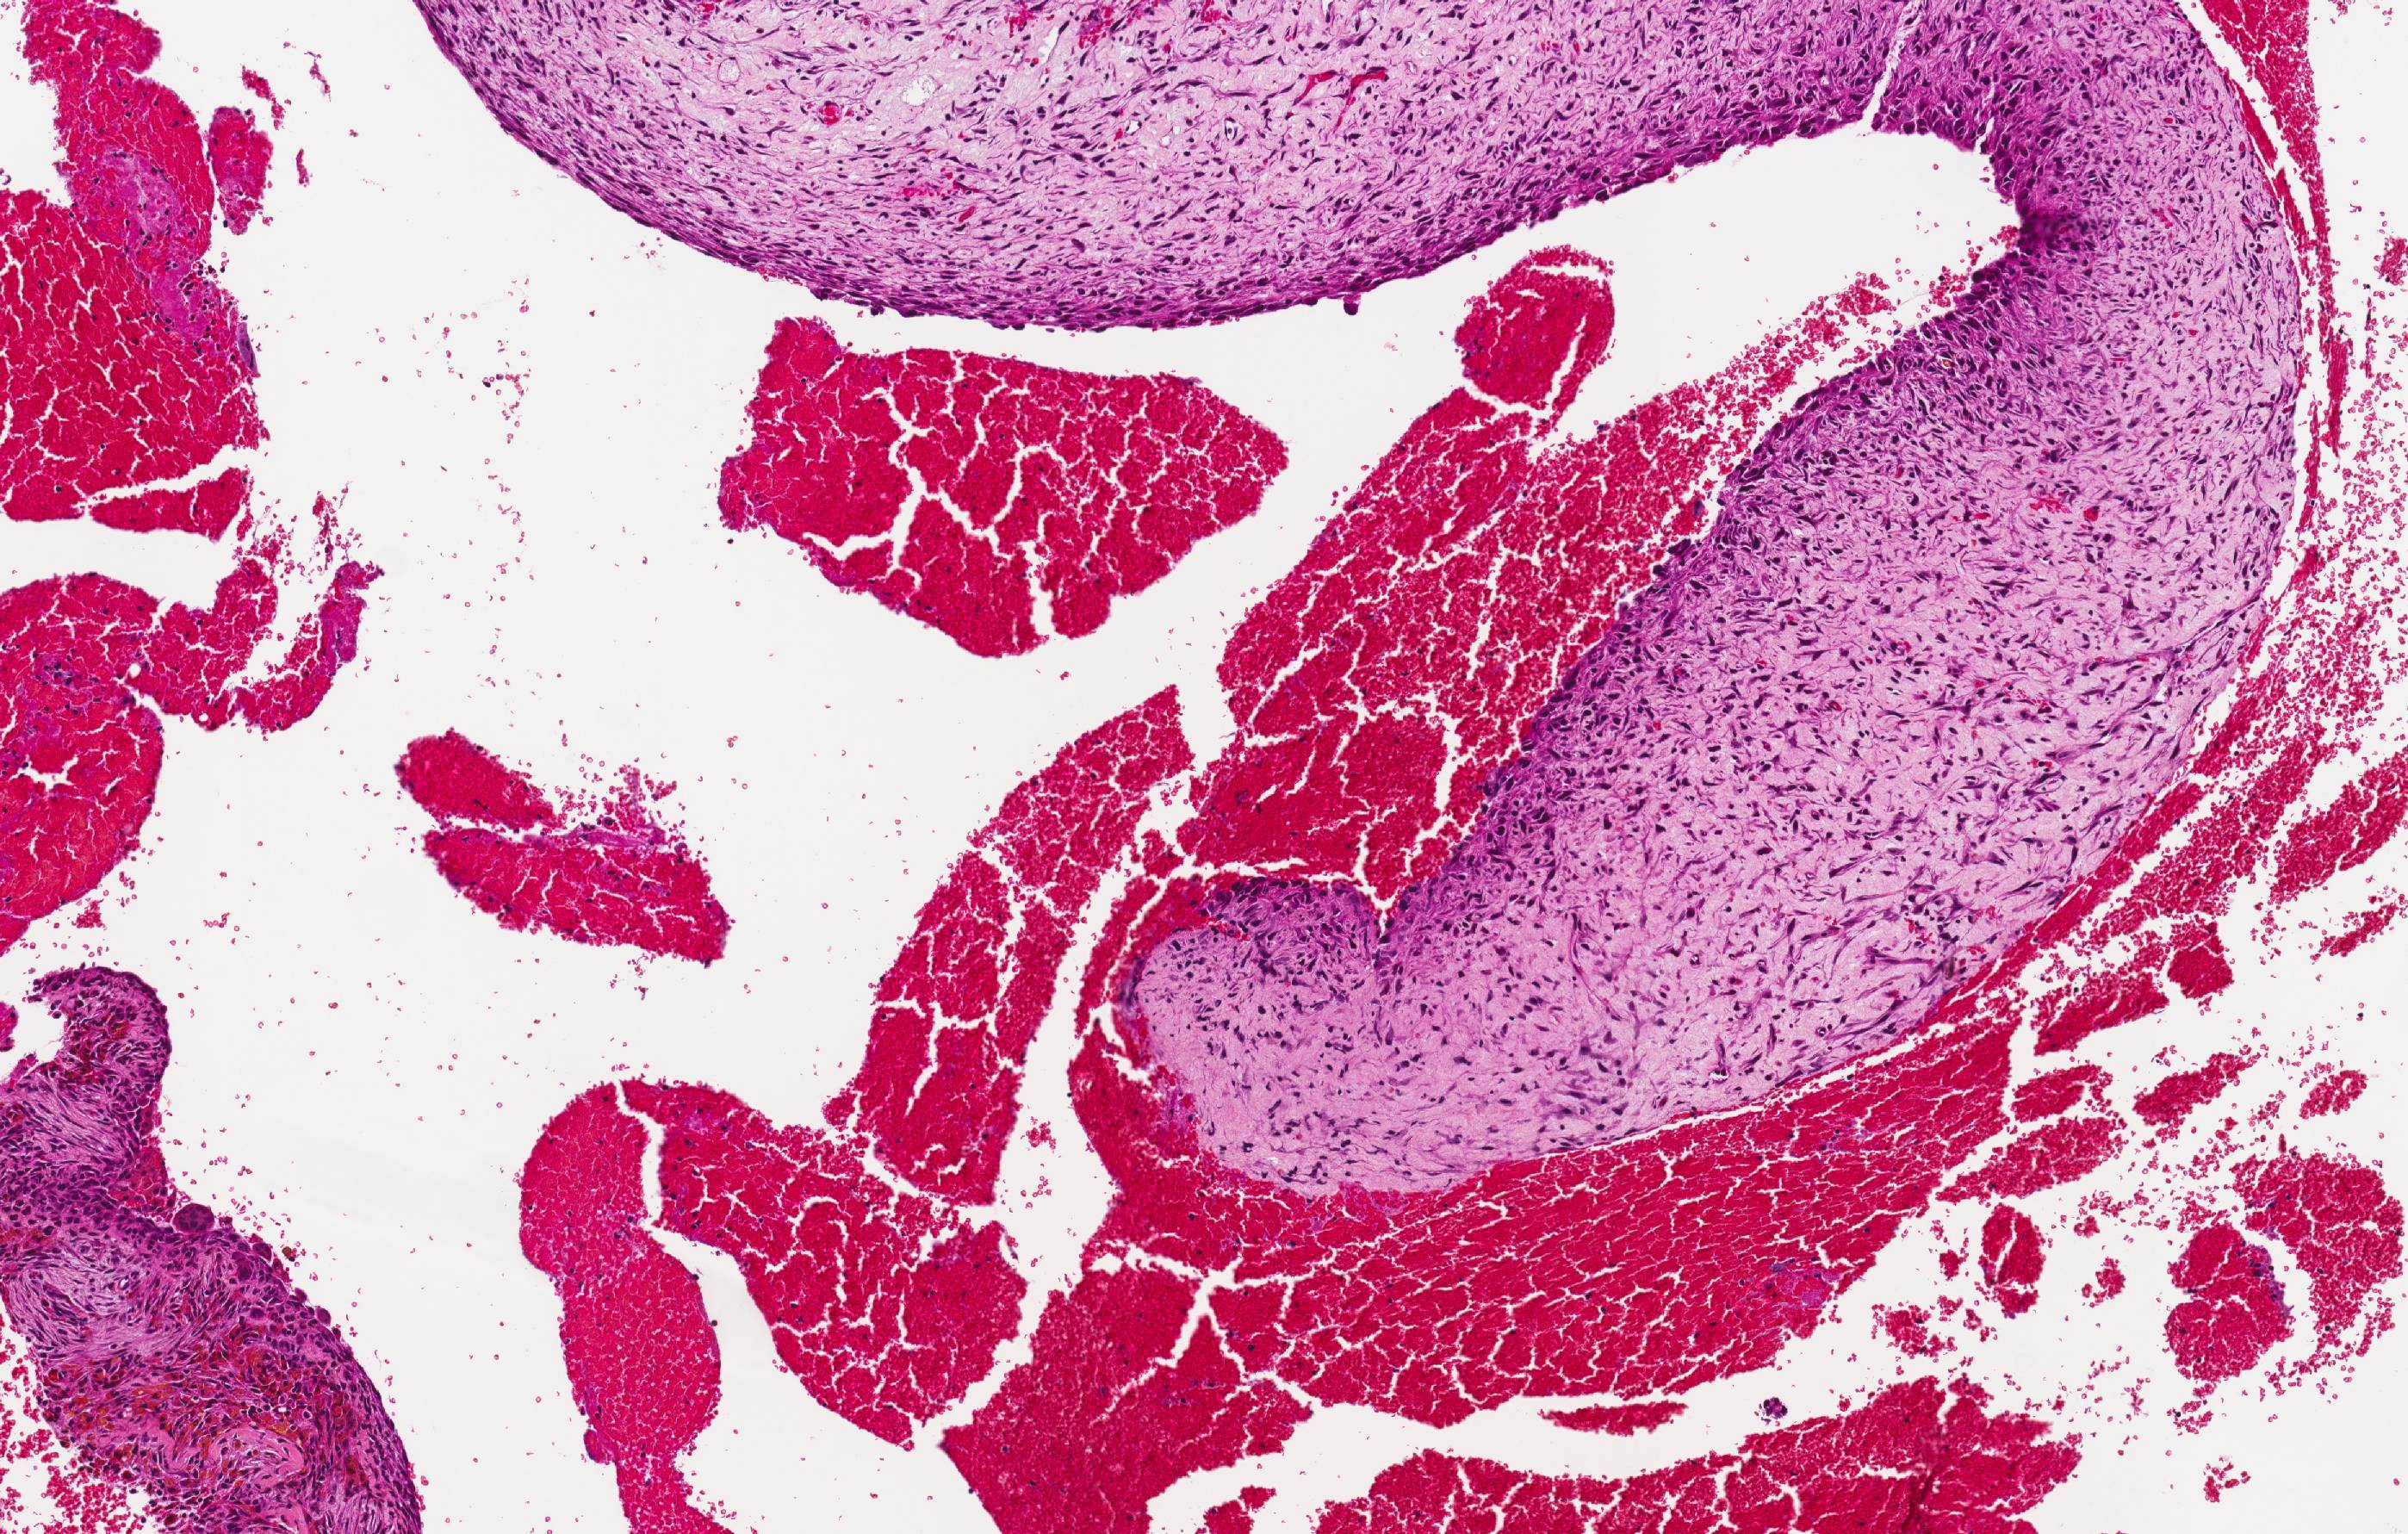

Gross description

- Spongy, multiloculated, hemorrhagic lesion

- Variable size

- Irregular, sharply demarcated borders with thin shell of reactive bone

- Variable amount of solid component

- Multiloculated cystic lesion

- Blood filled cystic spaces separated by cellular septa containing fibroblasts, giant cells and woven bone

Microscopic (histologic) images

Contributed by Elham Nasri, M.D. and Kelly Magliocca, D.D.S., M.P.H.